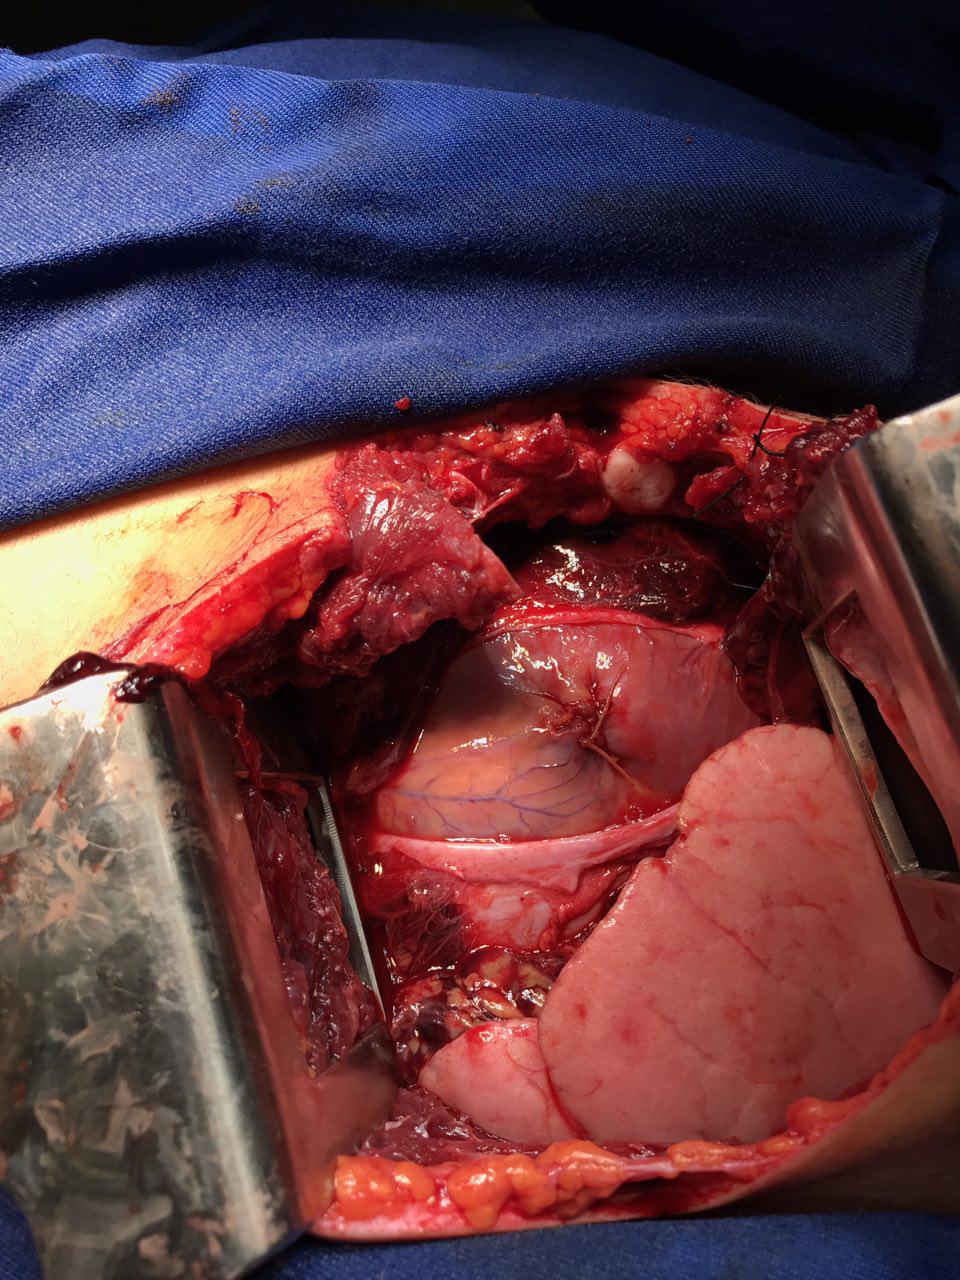

به گزارش روابط عمومی – دکتر رضا کرد رئیس بیمارستان امام خمینی (ره) خاش در این باره گفت: بر اثر اصابت چاقو، بطن راست قلب این جوان دچار پارگی و در نتیجه ایست قلبی شده بود.

وی ادامه داد: خوشبختانه عمل جراحی قلب بیمار با موفقیت انجام شد و در این ماه پر خیر و برکت این جوان،دوباره به زندگی بازگشت.